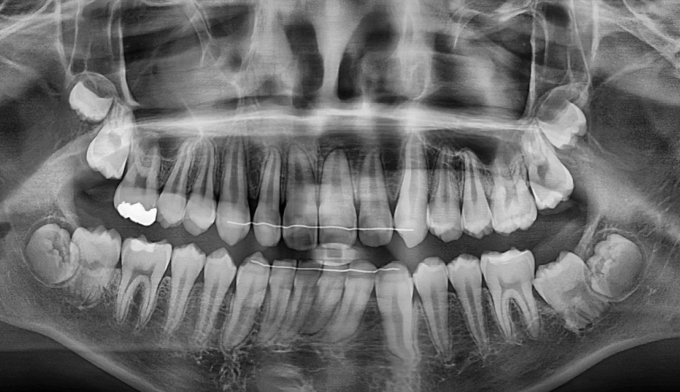

본 케이스에서는 위쪽과 아래쪽 송곳니 모두 치아 머리 주변으로 작은 물혹이 감싸고 있어 스스로 구강내로 나오지 못하고 있었습니다.

간단히 해당 위치를 절개 후 물혹을 제거해주고 치아를 제 위치로 이동시켰습니다.

총 교정기간은 13개월입니다.